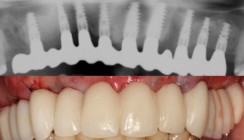

Während der Befundung stellte sich heraus, dass hier die Durchführung der navigierten Implantation mittels der bereits vorhandenen rein schleimhautgetragenen Bohrschablone nicht adäquat durchführbar war, da diese aufgrund einer starken Schleimhautresilienz, in Kombination mit der Lippen-Kiefer-Gaumen-Spalte nicht positionsstabil platziert werden konnte. Die unkomprimierten DICOM-Daten der vorhandenen DVT-Aufnahme wurden in die Planungssoftware Expert-Ease™ (DENTSPLY Implants) eingelesen. Es zeigte sich in einzelnen Regionen ein ausreichendes Knochenangebot mit einer ausreichenden Knochenqualität, welches voraussichtlich eine Sofortbelastung zuließ. Es wurden sechs Implantate (ANKYLOS®, DENTSPLY Implants) in den Regionen 16 (11mm/3,5 Ø), 15 (11mm/3,5 Ø), 14 (8mm/3,5 Ø), 25 (8mm/3,5 Ø), 26 (8mm/4,5 Ø), 27 (11mm/3,5 Ø) navigiert geplant (statische Navigation) (Abb. 2). Diese wurden im 3-D-Ansichtsmodus möglichst parallel ausgerichtet und in allen drei Ebenen überprüft (Abb. 3). Direkt nach Implantation sollte der Patient eine Sofortversorgung mit präfabrizierten SynCone® Aufbauten erhalten. Auch diese können virtuell unter funktionellen als auch unter ästhetischen Gesichtspunkten geplant werden. Die Planung mittels der ExpertEase™ Software, welche auf der SimPlant® Software Materialise (Leuwen, Belgien) basiert, wurde via Datenübertragung online versendet. Es wurde eine knochengetragene Bohrschablone gewählt, welche aufgrund der noch vorhandenen Lippen-Kiefer-Gaumen-Spalte im anterioren Bereich zweiteilig hergestellt wurde. Stereolithografisch wurden durch die Fa. Materialise Dental (Leuven, Belgien) zwei Modelle hergestellt, ein Knochen-Modell (Abb. 4) und ein Immediate Smile®-Modell mit Laboranalogen (Abb. 5). Das Knochen-Modell ist ein analog zum Oberkieferknochen, das Immediate Smile®-Modell ist ein anatomisches Duplikat der Knochensituation im Oberkiefer, in welchem bereits die Laboranaloge der geplanten Implantate integriert sind. Es wird also ein prothetisches Meistermodell bereits vor Implantation aus den virtuellen Daten erstellt.

Mittels des Immediate Smile-Modells® konnten die SynCone® Pfosten bereits präoperativ im Labor durch den Techniker parallel zueinander ausgerichtet werden, um die Pfosten dann mit einem ebenfalls im Labor hergestellten Übertragungsschlüssel zu positionieren (Abb. 9). Die SynCone® Pfosten wurden dann intraoperativ mittels des Übertragungsschlüssels eingesetzt und die präfabrizierten Sekundärteile in die vorhandene Prothese definitiv einpolymerisiert (Abb. 10–16). Der Wundverschluss erfolgte mittels Einzelknopfnähten. Abbildung 17 zeigt das postoperative Röntgenbild. Der Gaumenbereich der vorhandenen Prothese konnte direkt postoperativ freigeschliffen werden. Der Patient wurde angewiesen, die Prothese vier Wochen lang nicht selbst zu entfernen, ferner wurde eine weiche Diät verordnet. Lokal wurde der Patient angewiesen, dreimal täglich mindestens eine Minute mit einer 0,2-prozentigen Chlorhexidinlösung zu spülen.